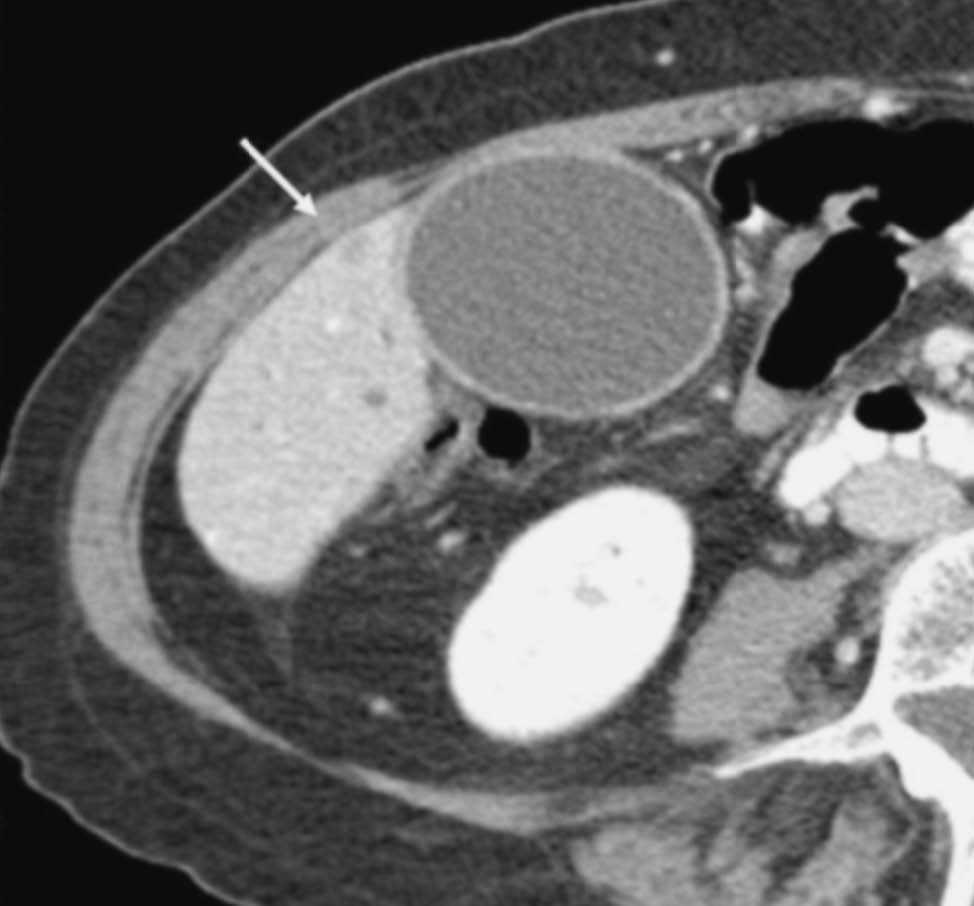

El estudio dinámico volumétrico tridimensional con saturación grasa permite una precisa visualización de las estructuras vasculares arteriales y venosas peripancreáticas50,51, lo que posibilita la evaluación de la extensión vascular local (fig. 11). Hochwald et al52 revisan retrospectivamente los estudios de RM y de colangiopancreatografía por RM (CPRM) de 21 pacientes con sospecha de cáncer de páncreas para determinar su resecabilidad. La técnica detectó todas las lesiones y mostró un rendimiento diagnóstico para diferenciar entre lesiones pancreáticas malignas y benignas del 81%, y del 43% para predecir la afectación ganglionar. En cuanto a la predicción de la resecabilidad tumoral, los autores describen una sensibilidad de la técnica del 100%, especificidad del 83%, valor predictivo positivo del 94% y negativo del 100%. La precisión diagnóstica de la RM, incluyendo la CPRM fue del 95%. Los buenos resultados que presentan estos autores muy probablemente se deben a que evalúan la rentabilidad de la RM en 21 pacientes con masa pancreática, aunque sólo 16 de ellos tenían un adenocarcinoma ductal pancreático (10 fueron resecados, mientras que los 6 restantes fueron irresecables). Los datos se han calculado sobre 15 tumores resecables sobre los 21 que constituyen la serie.

López Hänninen et al53, utilizando RM dinámica y CPRM, definen un valor predictivo positivo y negativo para neoplasia irresecable pancreática del 90 y 83% respectivamente, una sensibilidad y especificidad del 69 y 95% y un rendimiento global del 85%. Fischer et al54 presentan un valor predictivo positivo de la RM del 87% para la resecabilidad tumoral local cuando seleccionan sólo los tumores sólidos de su serie, que fueron 29 casos. Los autores definen esta técnica como la de mayor coste-eficacia y la proponen como la única a realizar en el diagnóstico de extensión del cáncer (fig. 12) de páncreas basándose en la política de «todo en uno»: toda la información requerida obtenida en una sola técnica diagnóstica.

Fig. 12.--Neoplasia irresecable de cuerpo pancreático. (A) Colangiorresonancia magnética que muestra una dilatación del conducto de Wirsung al nivel de la cola pancreática con stop brusco al nivel del cuerpo (puntas de flecha). (B) secuencia de resonancia magnética potenciada en T1 con saturación grasa tras la administración de contraste endovenoso. Masa heterogénea a nivel del cuerpo pancreático (puntas de flecha) que dilata el conducto de Wirsung. (C) angiorresonancia magnética en fase arterial. Se observa la arteria mesentérica superior permeable, pero ampliamente rodeada por el tumor pancreático (punta de flecha). (D) angiorresonancia magnética en fase venosa con estenosis severa del confluente porto-mesentérico (puntas de flecha).